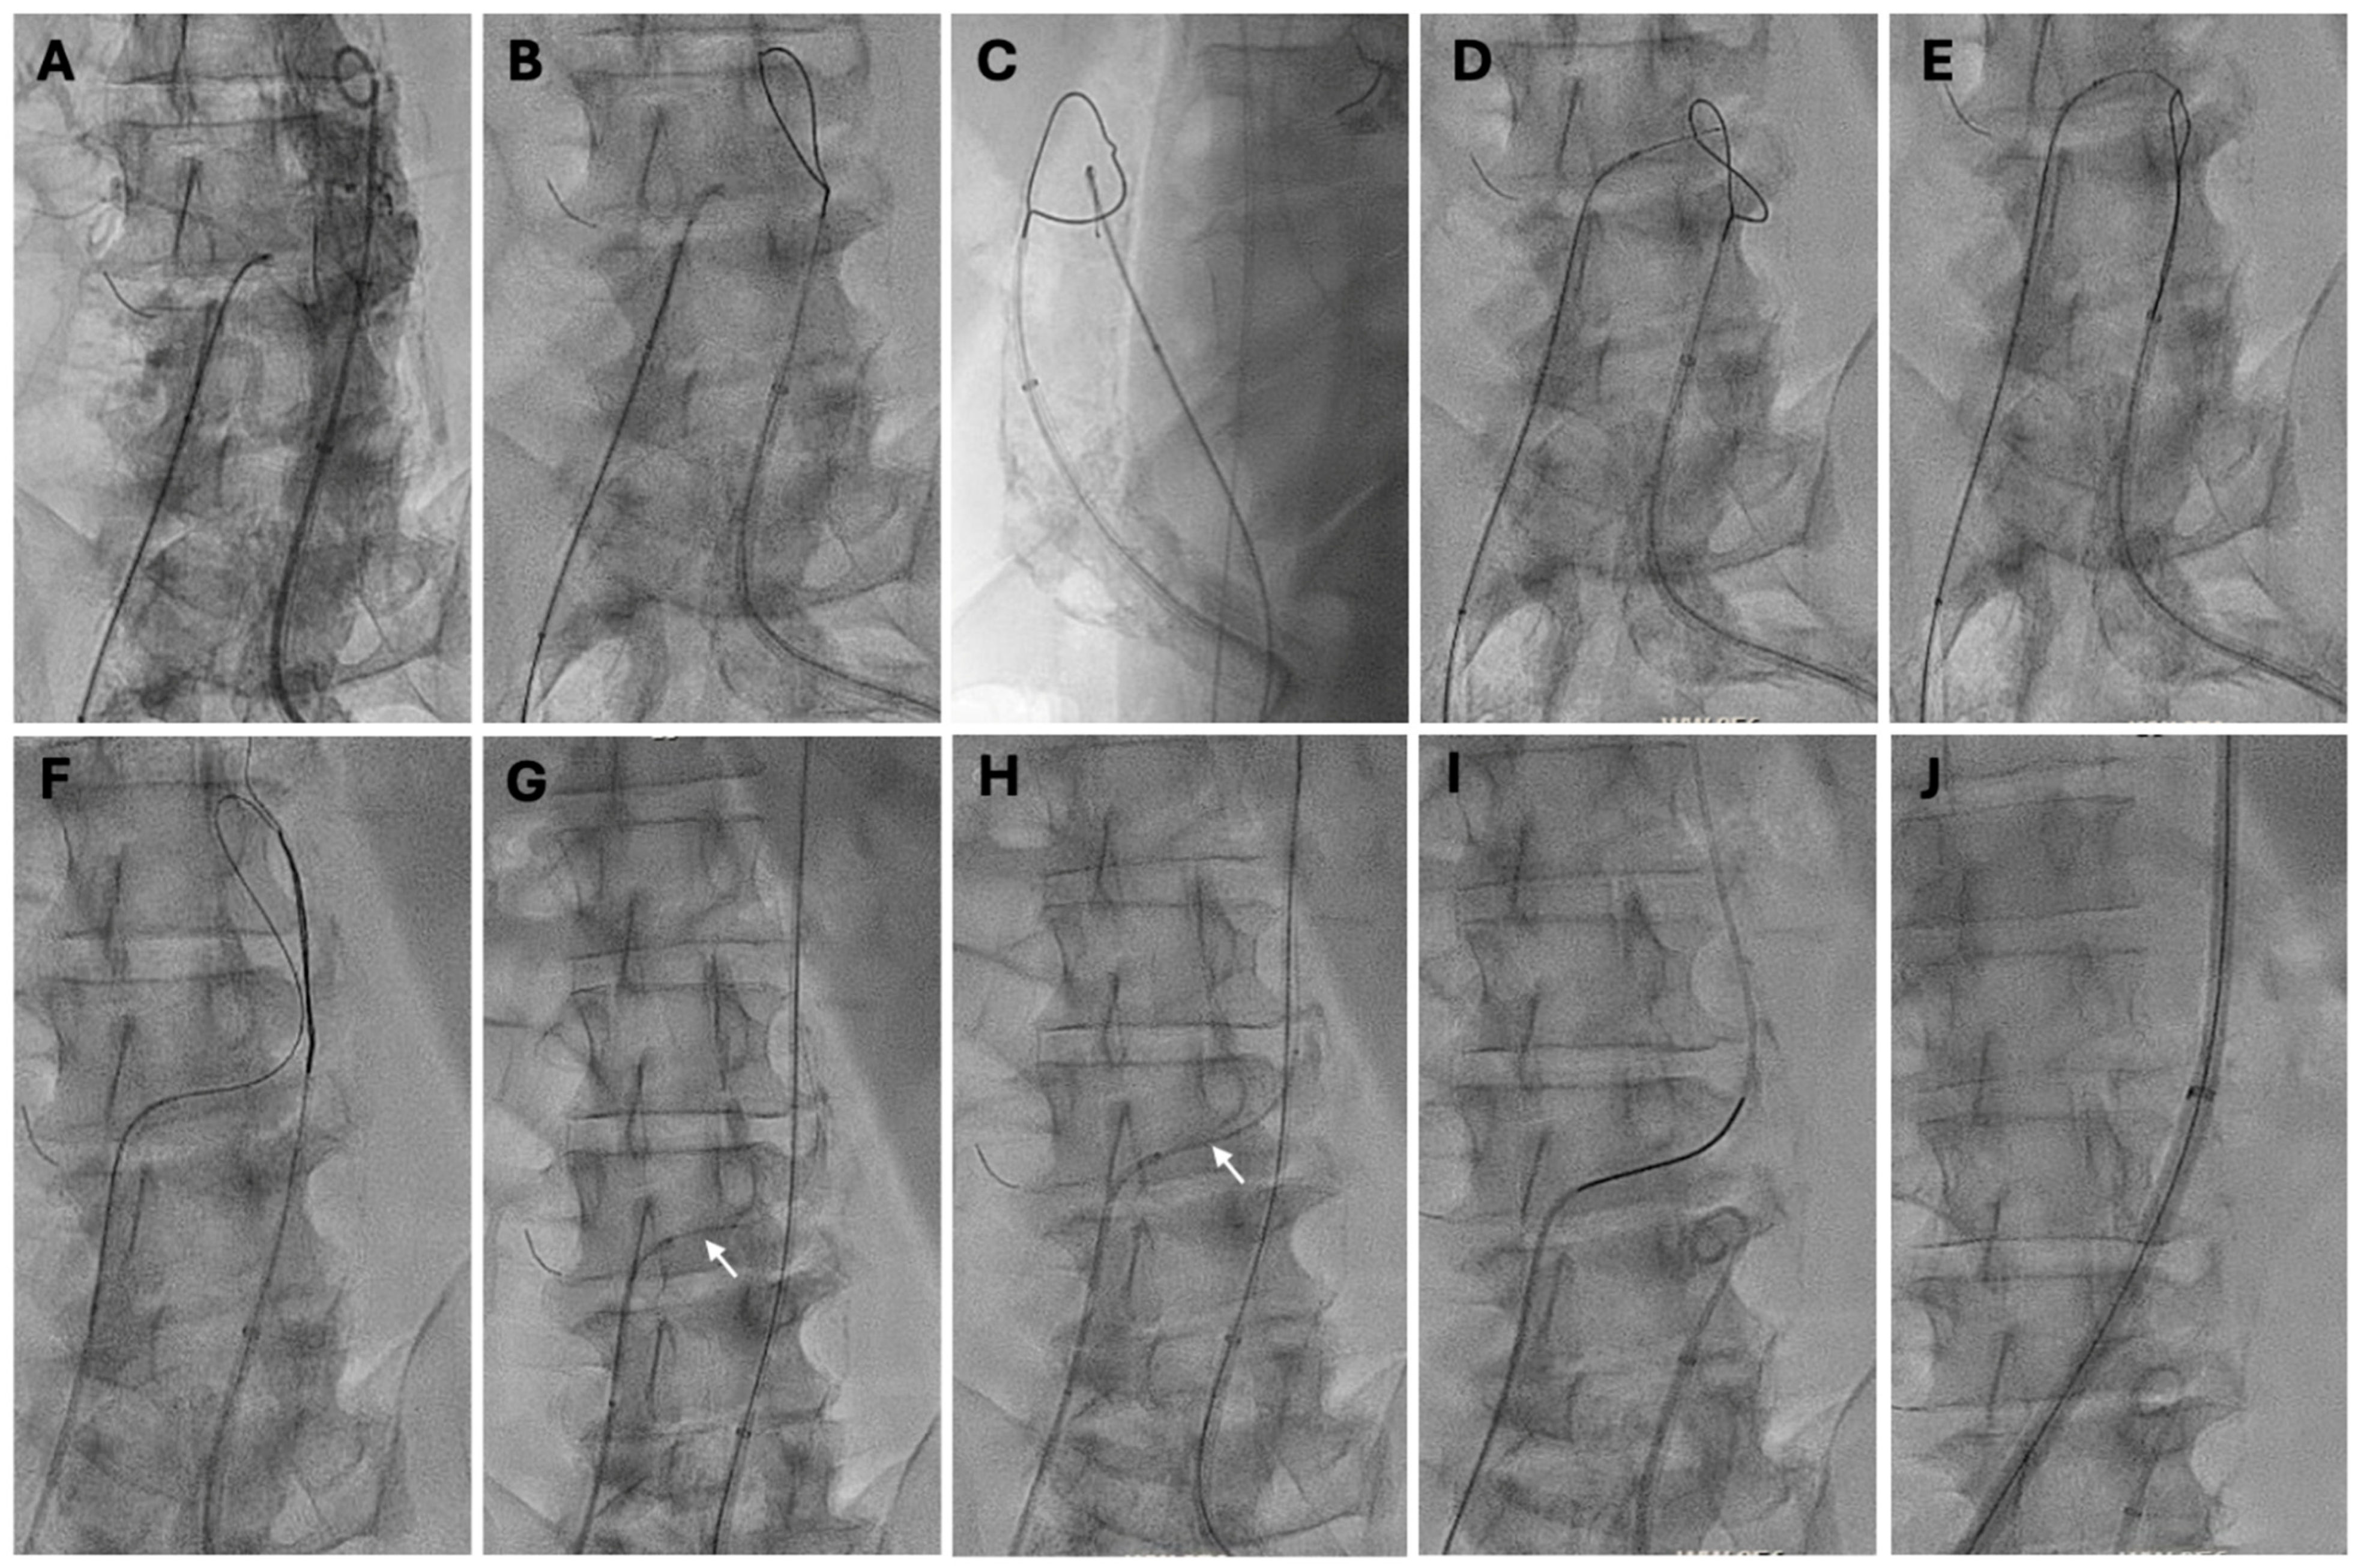

4.5.3. Transcaval Access Technique

- Lederman, R.J.; Babaliaros, V.C.; Greenbaum, A.B. How to Perform Transcaval Access and Closure for Transcatheter Aortic Valve Implantation. Catheter. Cardiovasc. Interv. 2015, 86, 1242–1254. [Google Scholar] [CrossRef] [PubMed]